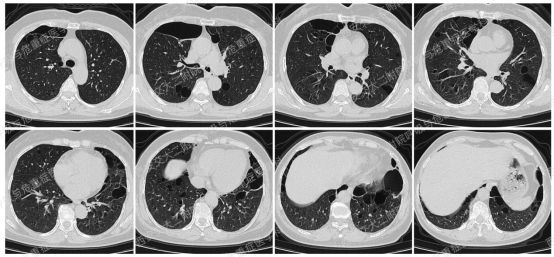

上图所示肺部多发囊性病变,双肺广泛分布,直径在2-10mm之间,壁薄,囊壁间组织相对正常。结合育龄期女性等临床资料,不难诊断淋巴管平滑肌瘤病(LAM)。对疑似LAM的女性的初步评估还应包括血管平滑肌脂肪瘤的筛查、淋巴管受累以及是否存在未被诊断的结节性硬化症。该例患者经评估后诊断散发型S-LAM。

该患者肺功能下降达到治疗标准,但患者及家属暂不考虑用药,选择观察,目前随访中。曾咨询乘飞机到拉萨的问题,鉴于症状稳定,可乘坐飞机,但不建议上高原。

Case 3

上图与Case 2比较相似,所以诊断LAM没有问题,还需进一步排查系散发型还是结节性硬化症累及。

影像学评估发现患者多系统受累(肝脏错构瘤、双肾血管平滑肌脂肪瘤、颅脑多发异常信号结节)。追问病史,患者本人无皮疹、癫痫及智力低下;患者儿子有面部皮脂腺瘤,无癫痫及智力低下,胸腹部CT未见异常,皮肤科已确诊结节性硬化症;患者女儿面容及智力均正常;建议患者进一步行TSC基因检测,结果回报TSC2突变,结节性硬化症诊断明确。

患者尝试口服西罗莫司2mg/日,消化道难以耐受,减至1mg/日,仍有恶心等不适,自行停药,不愿再尝试药物治疗,目前随访观察中。